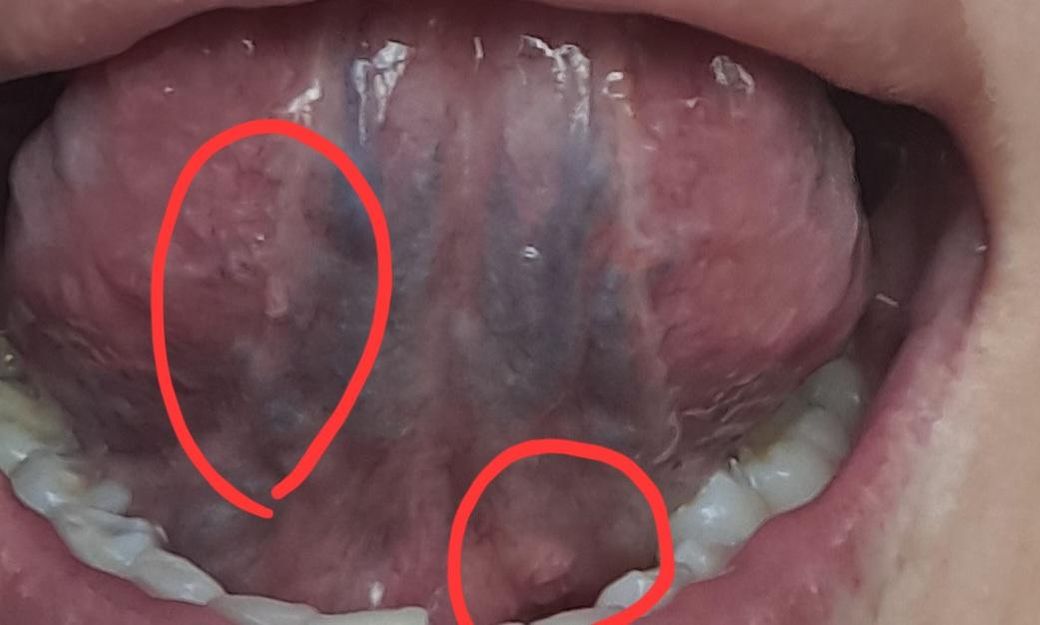

구강유두종 증상인지 궁금합니다. 병원은 어디로

최근 콘딜로마 치료중인데 혹시 구강에도 올라온것이 콘딜로마인지 정상조직인지 궁금합니다ㅜ 병원은 어디로 가야할까요? 치과인지 이비인후과인지...

• 1번 째 사진

특이소견으로 생각되지 않으나, 보다 적절한 평가 시행 위해 이비인후과 내원하여 진료 봐보실것 권유드립니다. 답변 도움되었기 바랍니다. 감사합니다.

콘딜로마의 가능성이 높아 보이지는 않습니다만, 진료를 받아보셔서 정확한 진단을 받아보시기를 바랍니다.

갯수가 늘어나거나 크기가 커지는 것이 아니라면, 임상적으로 콘딜로마의 가능성은 떨어집니다.